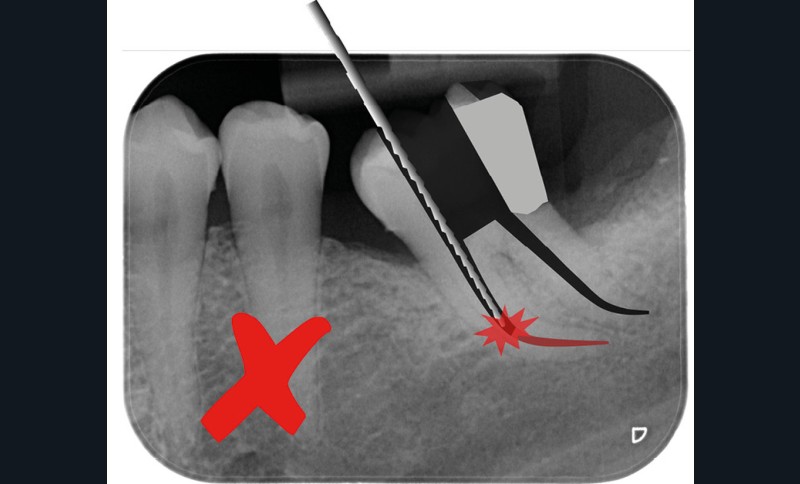

Trop petite

Une cavité d’accès trop petite [2] optimiserait le pronostic biomécanique (préservation dentaire maximale) mais pourrait compromettre le pronostic endodontique : mauvaise lecture de l’anatomie, instrumentation partielle, non ergonomique et avec risque de fracture, défaut de nettoyage des parois canalaires [3], irrigation inadéquate, difficulté d’obturation canalaire, voire d’obturation coronaire. Ce sera le cas des cavités d’accès « Ninja » [4] ou ultraconservatrice (fig. 1), des cavités d’accès « Truss » [5] (fig. 2), des cavités d’accès dites « opportunistes » [6] (fig. 3).